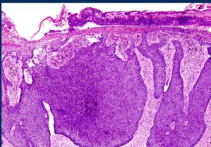

it arises from the basal cell layer of the epidermis as clusters of cells with dark stained blue nuclei.

palisade arrangement of the nuclei of the cells in periphery of the clusters.